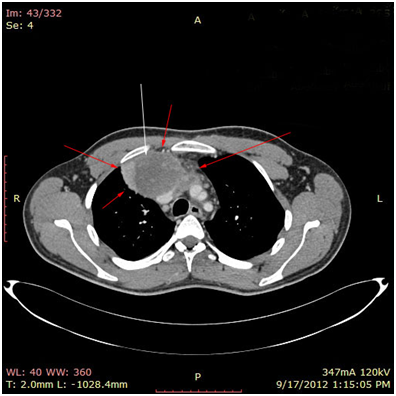

Bild 2 CT – axial plan of a large Yolk sac tumor in the anterior mediastinum invading the art. Carotis communis. White arrow pointing low attenuation foci, suggesting central necrosis.

Bild 3 CT – axial plan of the Yolk sac tumor.